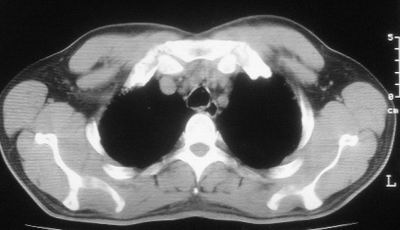

2\\少量腹水

1.双肺急性粟粒型肺结核;2.少量腹水.